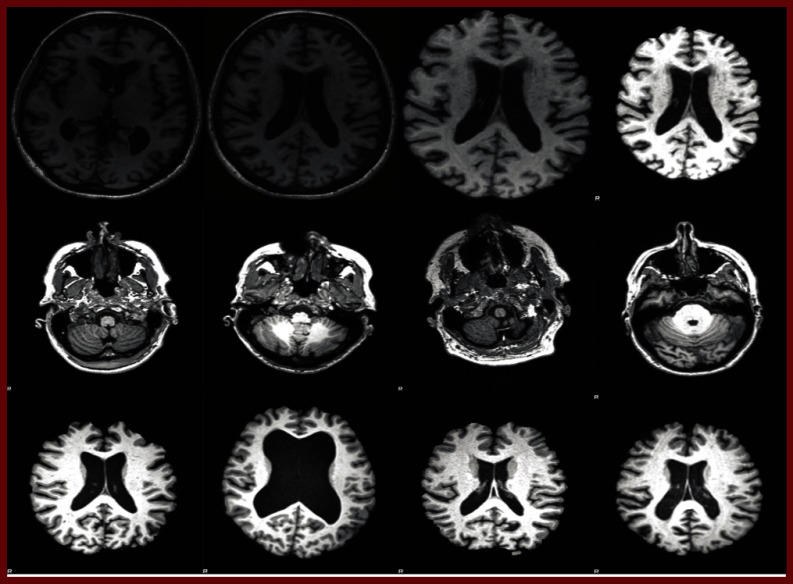

Transformers have dominated the landscape of Natural Language Processing (NLP) and revolutionalized generative AI applications. Vision Transformers (VT) have recently become a new state-of-the-art for computer vision applications. Motivated by the success of VTs in capturing short and long-range dependencies and their ability to handle class imbalance, this paper proposes an ensemble framework of VTs for the efficient classification of Alzheimer's Disease (AD). The framework consists of four vanilla VTs, and ensembles formed using hard and soft-voting approaches. The proposed model was tested using two popular AD datasets: OASIS and ADNI. The ADNI dataset was employed to assess the models' efficacy under imbalanced and data-scarce conditions. The ensemble of VT saw an improvement of around 2% compared to individual models. Furthermore, the results are compared with state-of-the-art and custom-built Convolutional Neural Network (CNN) architectures and Machine Learning (ML) models under varying data conditions. The experimental results demonstrated an overall performance gain of 4.14% and 4.72% accuracy over the ML and CNN algorithms, respectively. The study has also identified specific limitations and proposes avenues for future research. The codes used in the study are made publicly available.